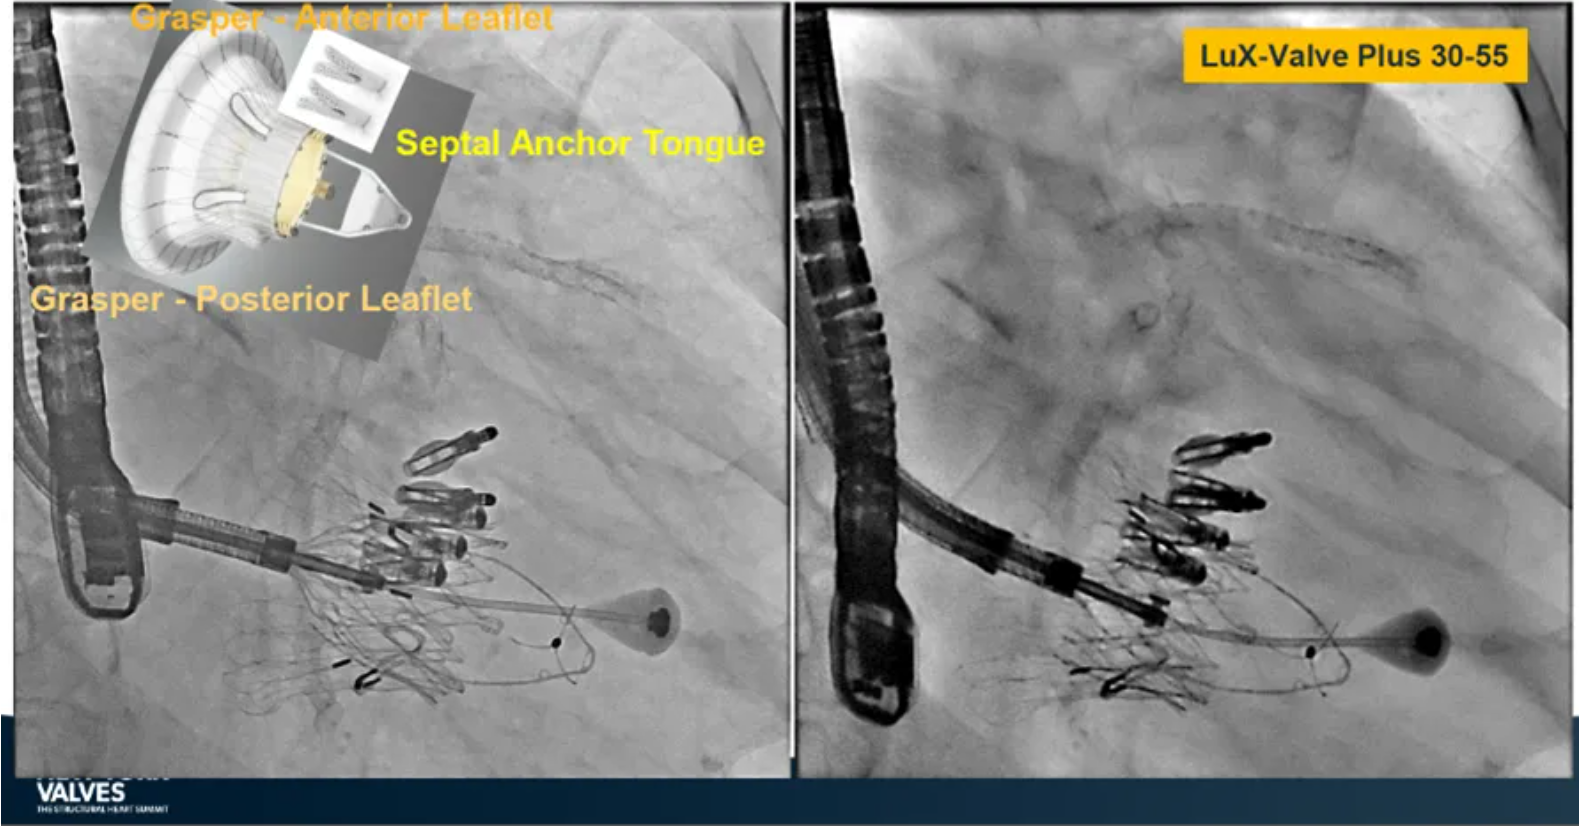

Granada教授表示,LuX-Valve Plus是一款不依賴于徑向支撐力固定的多功能TTVR器械,它的創(chuàng)新設(shè)計(jì)(室間隔錨定和瓣葉夾持件)提供了多樣的固定和穩(wěn)定技術(shù)。多中心臨床試驗(yàn)研究TRAVEL II 展現(xiàn)了LuX-Valve Plus的安全性和有效性,能實(shí)現(xiàn)較短的器械操作時間,較低的復(fù)合事件發(fā)生率,并在6個月期時顯著降低三尖瓣反流等級,以及帶來心功能和生活質(zhì)量等指標(biāo)上的明顯改善。

來自中國香港瑪麗醫(yī)院(Queen Mary Hospital, Hong Kong, China)的Simon Lam教授在2024紐約瓣膜會上分享了一例復(fù)雜案例,一名高齡男性患者在2年前行二尖瓣和三尖瓣TEER術(shù)式后繼發(fā)三尖瓣反流,遂再次行二尖瓣TEER術(shù)式和用LuX-Valve Plus行三尖瓣TTVR術(shù)式。

本次術(shù)式中,LuX-Valve Plus的植入緊隨二尖瓣修復(fù)術(shù)式之后,且并未取出前期植入的三尖瓣修復(fù)夾,這意味著LuX-Valve Plus在患者有過二尖瓣和三尖瓣修復(fù)夾植入情況下的兼容性,并且?guī)砹擞行У闹委熃Y(jié)果。此外,這不僅體現(xiàn)了LuX-Valve Plus可以與二尖瓣術(shù)式并行,更可以兼容三尖瓣原位的其他修復(fù)夾產(chǎn)品。

來自中國上海復(fù)旦大學(xué)附屬中山醫(yī)院的魏來教授在2024年臺北瓣膜高峰論壇上分享了他使用LuX-Valve Plus治療三尖瓣反流的經(jīng)驗(yàn)。魏來教授闡述道,隨著療法演變,目前全球市場有以LuX-Valve Plus及其他產(chǎn)品為代表的經(jīng)導(dǎo)管三尖瓣介入置換系統(tǒng),逐漸成為重度三尖瓣反流的一線治療方案。他介紹到,LuX-Valve Plus創(chuàng)新的室間隔錨定和經(jīng)頸靜脈入路的方式,能夠帶來安全穩(wěn)定的錨定效果及較短的輸送行程;其可調(diào)彎的輸送系統(tǒng)能保證同軸性,從而快速和安全地將人工瓣膜送達(dá)目標(biāo)手術(shù)區(qū)域,有效降低入路周邊解剖組織并發(fā)癥及術(shù)中出血風(fēng)險。